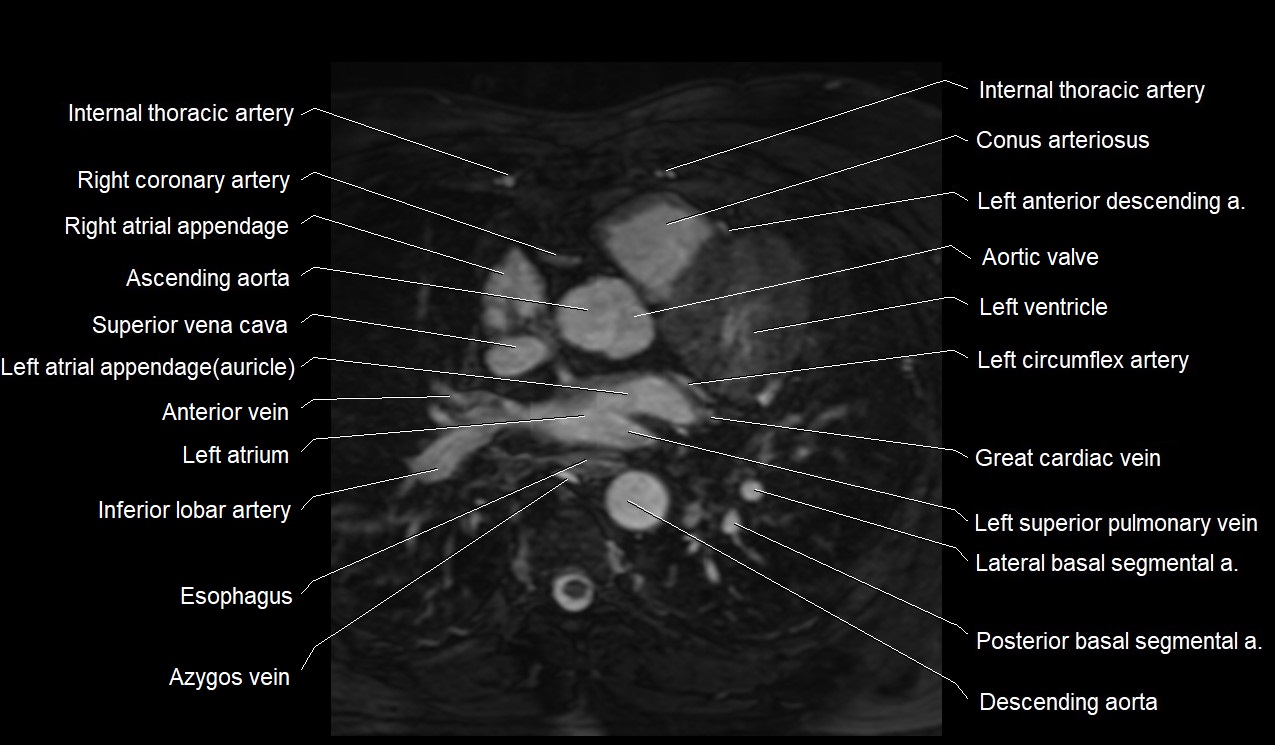

MRI image